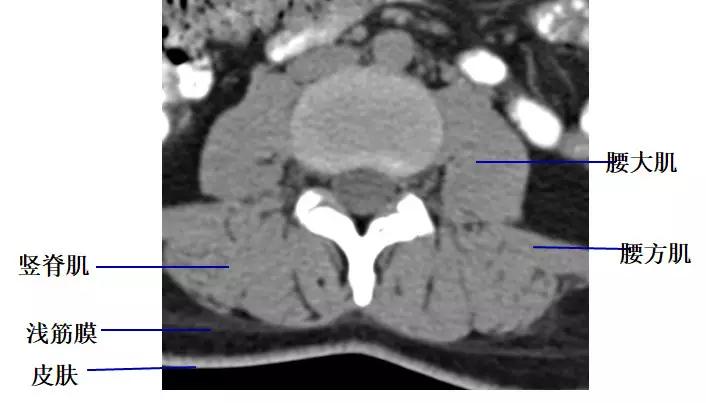

7.椎旁软组织

CT上均表现为软组织密度结构,CT值约40HU~50HU。